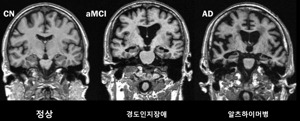

- 아래 그림은 실제 MRI/PET 영상에서 AI 모델이 자동으로 알츠하이머병 뇌위축 부위와 정상 부위를 색상으로 구분하여 진단을 도와주는 예시입니다.

위 그림은 AI 분석과정에서 MRI/PET 이미지로 알츠하이머병 진단에 중요한 뇌 영역이 파란색(병변), 녹색(정상) 등으로 색상 구분되어 시각적으로 제시되는 예시 절차도입니다.